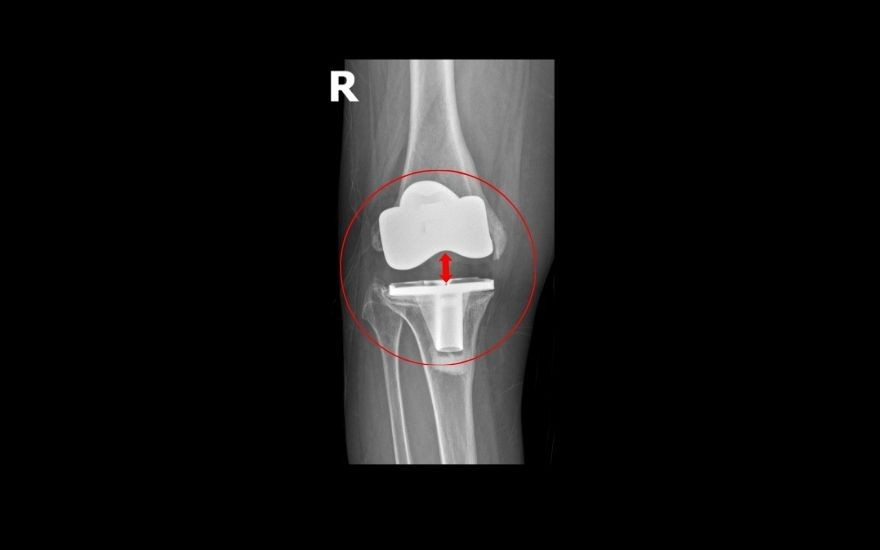

Một trường hợp hy hữu khác: 5 năm trước, bà Oanh (63 tuổi) bị thoái hóa khớp gối độ IV nghiêm trọng, nên đã quyết định phẫu thuật thay khớp gối để cải thiện vận động. Khoảng một năm trở lại đây, khớp gối ngày càng sưng đau, lỏng lẻo, chân cong vẹo, khiến bà không thể đứng vững.

Vào thăm khám tại Bệnh viện Đa khoa Hồng Ngọc - Phúc Trường Minh, các bác sĩ phát hiện khớp gối nhân tạo của bà đã bị “trôi” khỏi ổ khớp. Theo TS.BS Lê Quang Huy, Trưởng khoa Ngoại Chấn thương chỉnh hình - Thần kinh sọ não: “Trường hợp của bệnh nhân Oanh hiếm gặp. Chỉ sau gần 5 năm phẫu thuật, phần kim loại bao bọc đầu dưới xương đùi đã lún vào lồi cầu trong xương đùi gần 2cm, khiến khớp gối lệch khỏi vị trí ban đầu".

Giải pháp duy nhất để phục hồi vận động và ngăn ngừa nguy cơ tàn phế là phẫu thuật thay lại khớp gối. Ca mổ của bà Oanh được đánh giá là phức tạp do gân cơ, dây chằng và cấu trúc xương quanh khớp tổn hại nghiêm trọng, đòi hỏi bác sĩ tính toán kỹ lưỡng để vừa khôi phục trục chân nguyên bản, vừa bảo tồn tối đa gân cơ, hạn chế biến chứng tái phát.

Sau khi hội chẩn cùng GS. Hiranaka Takafumi (Giám đốc Trung tâm Phẫu thuật Khớp, Bệnh viện Takatsuki, Nhật Bản), TS.BS Lê Quang Huy quyết định loại bỏ khớp nhân tạo cũ, thay thế khớp mới bằng kỹ thuật thay khớp gối gióng trục động học, không cắt gân cơ với đường mổ nhỏ, giúp bệnh nhân ít đau, có thể đi lại sau 1 - 2 ngày.

Ngoài ra, bác sĩ sử dụng khớp bản lề chuôi dài để tăng độ vững, khôi phục trục chân, giúp người bệnh khôi phục chức năng và tầm vận động, hạn chế nguy cơ di lệch khớp. Sau 2 giờ, ca mổ diễn ra thuận lợi. Khớp gối mới vừa vặn với ổ khớp, trục chân nguyên bản được khôi phục.